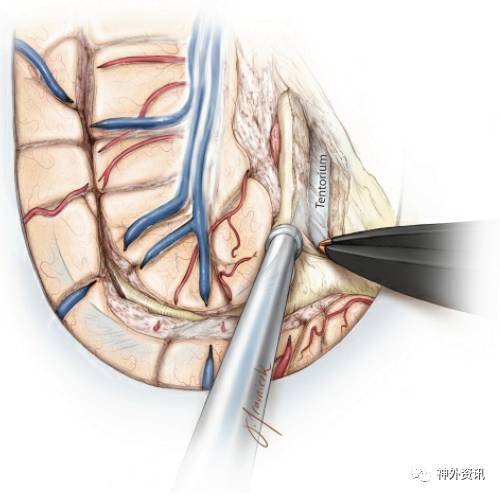

图13. 完成胼胝体离断术后,注意力转向后部的海马切除术。行海马切除术时,需要显露小脑幕的水平边缘,同时切除海马尾部的幕下部分。沿着禽距和侧脑室房部内侧面解剖白质,可以允许我沿着天幕幕下部分的水平边缘,找到幕上需要切除的白质。

图14. 待最后的胼胝体压部,禽距,海马尾部,穹窿小柱,楔状叶,楔前叶都被分离后,继续向上分离至天幕的幕上部分。沿着天幕和大脑镰交汇的地方继续追溯可以更好的帮助外科医生沿着胼胝体压部来分离白质纤维。天幕的水平段和上升段以及大脑镰可以帮助手术者定位。

图15. 大脑镰的后缘可以帮助术者找到天幕。在切除的过程中需要谨慎的进行软膜下分离,保护大脑后动脉穿过内侧和下方蛛网膜的分支。对于侧脑室房部的分离需要在脉络丛后方进行,这样可以保护丘脑。